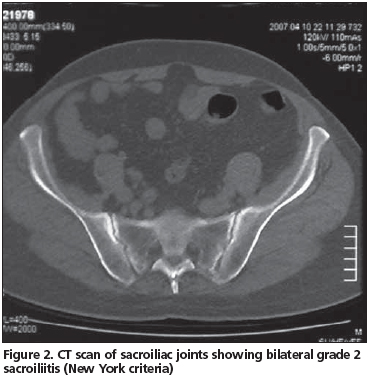

Cervical spine X-rays revealed flattening of the cervical lordosis with ankylosis and irregularity of the apophyseal joints at the C2-C5 level. Anterior and posterior syndesmophyte bridging with calcification of the spinal ligaments was observed on his thoracic spine radiographs. However, no radiological findings, except for flattening of the lumbar lordosis, were detected on the lumbar spine radiographs. The anteroposterior radiograph of the pelvis showed marked narrowing of the joint spaces and sclerosis on the acetabular surface of both hip joints. The computerized tomography (CT) scan of the sacroiliac joints revealed bilateral grade 2 sacroiliitis, according to the classical New York criteria (Figure 2).

Radiological changes in AS patients are seen rarely in the cervical region compared to thoracic and lumbar regions[2]. In contrast, the radiological changes of our case were more prominent in the cervical and thoracic regions, and no characteristic radiological findings of AS were observed in the lumbar region. Researchers have reported that cervical involvement could be more prominent in female patients[4,5]. Inconsistent with this data, our patient was male, but radiological change in his cervical spine was prominent. The CT scan of the sacroiliac joints showed bilateral grade 2 sacroiliitis. Olivieri et al.[5] found sacroiliitis in 30% of patients with BD. In parallel with these clinical reports, we also agree that sacroiliitis in BD should not be considered as a characteristic feature of the disease. Similar to our case, AS may coexist with BD. Therefore, this coexistence should be kept in mind.